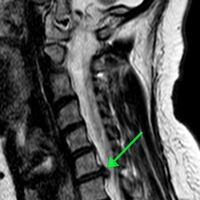

Пациентка обратилась с жлобами на изматывающую боль в руке. Ей провели МРТ, которое показало, что в шейном отделе сформировалась грыжа размером 8 мм. По словам медиков, образование сдавливало спинномозговой канал и корешковое отверстие, угрожая двигательной функции.

«Мы провели сложнейшее микрохирургическое вмешательство, в ходе которого удалили грыжу и стабилизировали позвоночник с помощью современного импланта», — рассказал нейрохирург Николай Карпов, отметив, что операция длилась два часа 20 минут.